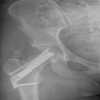

A 34-year-old male sustained a high-energy femoral shaft fracture with a concomitant low-energy, undisplaced, basicervical Garden’s type I, Pauwel’s type II femoral neck fracture. The neck fracture was stabilized anatomically in situ with compression using the FNS, with good implant positioning but a slightly lower tip-apex distance. At 5 months, the femoral neck had united (confirmed with computed tomography) (Fig. 5), but the shaft fracture had gone into non-union, for which exchange nailing and grafting were planned.

Figure 5: Radiographs (left) and computed tomography (top right) confirming complete fracture union in Case 6. Bottom center and right: immediate post-operative radiographs.